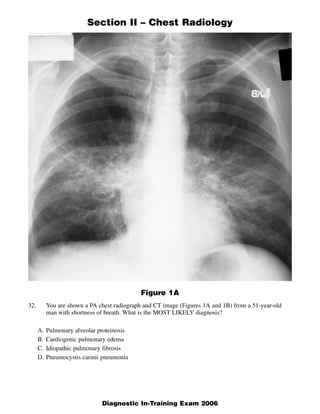

- 1. Section II – Chest Radiology Figure 1A 32. You are shown a PA chest radiograph and CT image (Figures 1A and 1B) from a 51-year-old man with shortness of breath. What is the MOST LIKELY diagnosis? A. Pulmonary alveolar proteinosis B. Cardiogenic pulmonary edema C. Idiopathic pulmonary fibrosis D. Pneumocystis carinii pneumonia 1 Diagnostic In-Training Exam 2006

- 3. Section II – Chest Radiology Question #32 Findings: Chest radiograph demonstrates bilateral perihilar opacities. High resolution CT scan demon- strates bilateral thin walled cysts, ground glass and reticular opacities Rationales: A. Incorrect. The most common radiographic manifestation of pulmonary alveolar proteinosis is ground glass and air space opacities which are located in a perihilar distribution such as in this case. The presence of ground glass opacities on the CT scan is consistent with pulmonary alveolar pro- teinosis. However, septal thickening is not prominent. The combination of ground glass opacities and septal thickening is sometimes referred to “crazy paving,” an appearance most commonly seen in pulmonary alveolar proteinosis. The CT also demonstrates the presence of multiple relatively thin walled cysts. Such cysts are not a feature of pulmonary alveolar proteinosis. B. Incorrect. Although the standard radiograph is somewhat suggestive of the “butterfly” or “bats wing” pattern identified in cardiogenic pulmonary edema, the heart is not enlarged and there is no evidence of Kerley B lines or pleural effusions. Multiple thin walled cysts are not a feature of con- gestive heart failure. C. Incorrect. IPF occurs in patients between 50 and 70 years old. Radiographic findings include reticu- lar opacities in the peripheral distribution at the lung bases. Thus, the presence of perihilar disease in our case along with absence of disease in the subpleural basilar location lead us away from the diagnosis. D. Correct. In patients with PCP, the chest radiograph classically demonstrates bilateral often perihilar reticular and ground glass opacification which may eventually become confluent and produce air space consolidation within several days. Cysts are visible on chest radiographs in 10% of patients although they are appreciated far more commonly on HRCT scans (33%). Cysts may occur in the acute or post infective period and range in number, size, shape and distribution. They are commonly multiple and have a predilection for the upper lobes. Spontaneous pneumothorax may be a feature of PCP infection and occurs in approximately 35% of patients with cysts. 3 Diagnostic In-Training Exam 2006